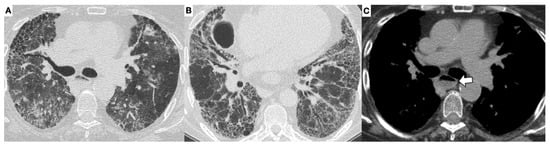

3.1. High-Resolution Computed Tomography in SSc-ILD: Qualitative Evaluation

- Orlandi, M.; Landini, N.; Sambataro, G.; Nardi, C.; Tofani, L.; Bruni, C.; Randone, S.B.; Blagojevic, J.; Melchiorre, D.; Hughes, M.; et al. The role of chest CT in deciphering interstitial lung involvement: Systemic sclerosis versus COVID-19. Rheumatology 2021, 28, 615. [Google Scholar] [CrossRef]

- Ruaro, B.; Baratella, E.; Confalonieri, P.; Wade, B.; Marrocchio, C.; Geri, P.; Busca, A.; Pozzan, R.; Andrisano, A.G.; Cova, M.A.; et al. High-Resolution Computed Tomography: Lights and Shadows in Improving Care for SSc-ILD Patients. Diagnostics 2021, 11, 1960. [Google Scholar] [CrossRef] [PubMed]

- Desai, S.R.; Veeraraghavan, S.; Hansell, D.M.; Nikolakopolou, A.; Goh, N.S.; Nicholson, A.G.; Colby, T.V.; Denton, C.P.; Black, C.M.; Du Bois, R.M.; et al. CT features of lung disease in patients with systemic sclerosis: Comparison with idiopathic pulmonary fibrosis and non-specific interstitial pneumonia. Radiology 2004, 232, 560–567. [Google Scholar] [CrossRef] [PubMed]

- Launay, D.; Remy-Jardin, M.; Michon-Pasturel, U.; Mastora, I.; Hachulla, E.; Lambert, M.; Delannoy, V.; Queyrel, V.; Duhamel, A.; Matran, R.; et al. High resolution computed tomography in fibrosing alveolitis associated with systemic sclerosis. J. Rheumatol. 2006, 33, 1789–1801. [Google Scholar]

- Yoo, H.; Hino, T.; Han, J.; Franks, T.J.; Im, Y.; Hatabu, H.; Chung, M.P.; Lee, K.S. Connective tissue disease-related interstitial lung disease (CTD-ILD) and interstitial lung abnormality (ILA): Evolving concept of CT findings, pathology and management. Eur. J. Radiol. Open 2020, 8, 100311. [Google Scholar] [CrossRef]

- Remy-Jardin, M.; Giraud, F.; Remy, J.; Copin, M.C.; Gosselin, B.; Duhamel, A. Importance of ground-glass attenuation in chronic diffuse infiltrative lung disease: Pathologic-CT correlation. Radiology 1993, 189, 693–698. [Google Scholar] [CrossRef] [PubMed]

- Shah, R.M.; Jimenez, S.; Wechsler, R. Significance of Ground-glass Opacity on HRCT in Long-term Follow-up of Patients With Systemic Sclerosis. J. Thorac. Imaging 2007, 22, 120–124. [Google Scholar] [CrossRef]